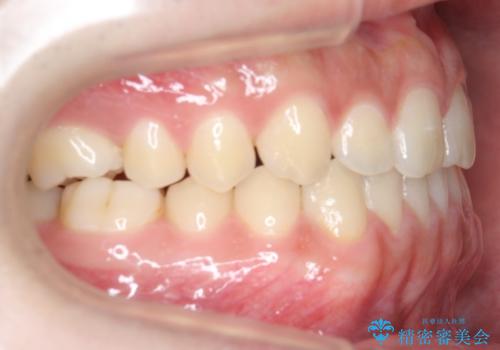

前歯のすきま 受け口 インビザラインで

- 前歯のすき間を気にして来院。

受け口もあり、前歯が端同士であたる、切端咬合となっていました。

下の歯のすき間を閉じて上の歯の内側に入るように位置付けました。

上の前歯は下の歯と直接へりが当たっていた状態(切端咬合)だったため、形がいびつだったのは、わずかにやすりがけをして整えました。

セラミックですき間を閉じようとすると、すきまをうめるために巨大な歯になり、また、下の歯が前に出て強く当たるため、セラミックがかけるおそれがあります。また、下の歯をさけようとすると角度をかえるために歯を極端に削らなければならなくなり、神経をとらなければいけなくなるリスクもあります。

このような歯並びは、セラミックでかぶせるよりは、矯正治療の

適応と言えます。